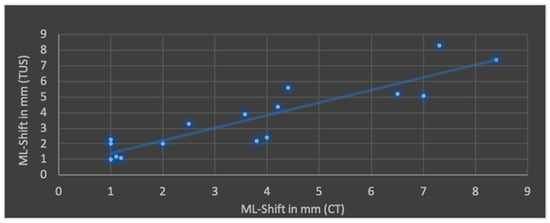

The Pearson’s correlation coefficient (r), including mean values and standard deviation of both modalities in terms of ML shift, lateral ventricular width, subdural space and ICH is shown in Figure 4, Figure 5, Figure 6 and Figure 7.

Figure 4.

Correlation of transcranial ultrasound (TUS) and computed tomography (CT) in terms of midline (ML) shift (r = 0.90; p < 0.001; mean value TUS: 3.6 ± 2.2 mm; mean value CT: 3.7 ± 2.5 mm).

The best correlation represented by Pearson’s correlation coefficient was shown in ML shift and lateral ventricular width. The evaluation of ICHs in TUS revealed a slightly weaker correlation, but with a p-value below 0.05, still indicating significance at the standard level. No significant correlation was found in terms of subdural space between both modalities; mean values obtained through CT were higher than those in TUS.

Regarding the application of TUS in post-craniectomy patients, the literature predominantly consists of case studies and studies with small patient cohorts [,,,]. Only a few studies compare CT and TUS in terms of visualizing relevant structures, and they are mostly obtained through the temporal acoustic window in non-craniectomized patients [,,,]. In a recently published prospective pilot study by Chouhan et al., 40 post-hemicraniectomy patients were examined. A strong correlation between both imaging modalities was observed in terms of ventricular width. However, a high standard deviation for ultrasound measurements was noted in a few patients with a severely enlarged ventricular system. Identification of hyperechoic lesions was described as more effective than hypoechoic ones. A correlation of lesion size (diameter or volume) was not performed. The working group describes the curved transducer as the most useful for this purpose. This corresponds with our study, where a curved probe was also selected []. In an older study by Bendella et al., 102 patients were examined using TUS. Ultrasound was performed no later than 24 h after cranial CT, which corresponds with our time frame. A strong correlation was found for ventricular diameters and ML shift. In this analysis, as in our study, the Pearson correlation coefficient was determined. Regarding lateral ventricular width and ML shift, slightly higher coefficients were observed here, although both study results are statistically significant. It cannot be ruled out that the prospective design and standardized study protocol as well as the larger patient number contributed to this outcome. TUS examinations were performed by three experienced investigators, analogous to our study. A qualitative assessment of the examiner subgroups was not conducted [].